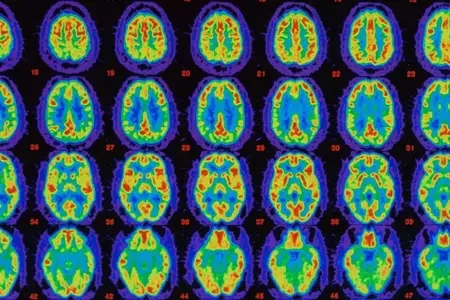

Учёные нашли связь между менопаузой и болезнью Альцгеймера